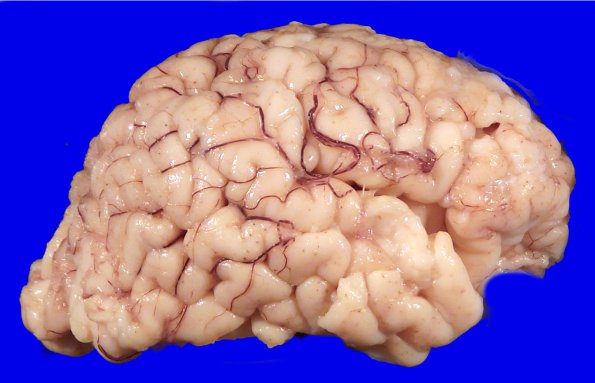

The gross appearance of the brain is fairly normal, although the cerebellar hemispheres appear somewhat atrophic.